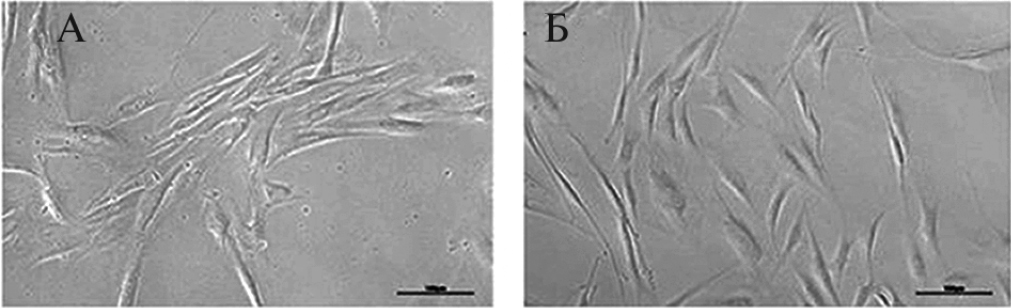

В настоящем исследовании, методом прямого репрограммирования, нами получены нейроны стриатума из линии дермальных фибробластов HDDF от пациента с БХ и контрольных клеток линии DF1 от здорового донора [18]. На рис. 1 представлен общий вид культуры дермальных фибробластов in vitro от пациента с БХ и от донора без нейропатологии. Показано, что хантингтин распределен диффузно в цитоплазме обеих популяций фибробластов без видимых агрегатов (рис. 2). Однако существенное отличие наблюдается в нейронах стриатума, полученных из этих фибробластов. На рис. 3 показано, что в нейронах, полученных из фибробластов линии DF1, хантингтин по-прежнему распределен диффузно по цитоплазме и видимых агрегатов не образует. Вместе с тем, в нейронах, полученных из фибробластов линии HDDF, были визуализированы агрегаты хантингтина в соме нейронов и в некоторых отростках этих клеток.

Рис. 1. Микрофотографии дермальных фибробластов человека in vitro. (а) Фибробласты линии DF1 (получены от здорового донора) и (б) линии HDDF (получены от донора с болезнью Хантингтона). Фазово-контрастная микроскопия, х10. Масштаб 100 мкм.